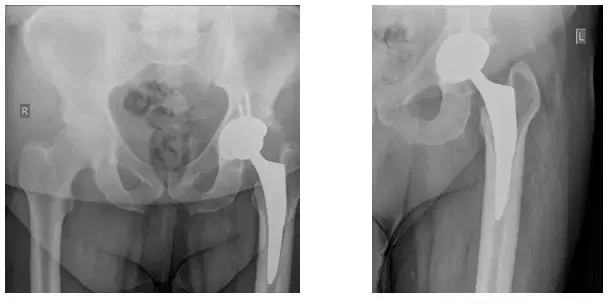

Quatre vues ont été prises : AP Pelvis (en haut à gauche), AP gauche Hanche (en haut à droite), Grenouille latérale gauche (en bas à gauche), Grenouille latérale droite (en bas à droite)

Les radiographies révèlent une ostéolyse dans l’acétabulum avec un relâchement possible de la composante fémorale. Le relâchement est mieux vu par rapport à la radiographie antérieure.